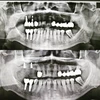

Diş Çürükleri

Diş Eksikliği

Diş ve Diş eti hastalıkları

Periimplantitis